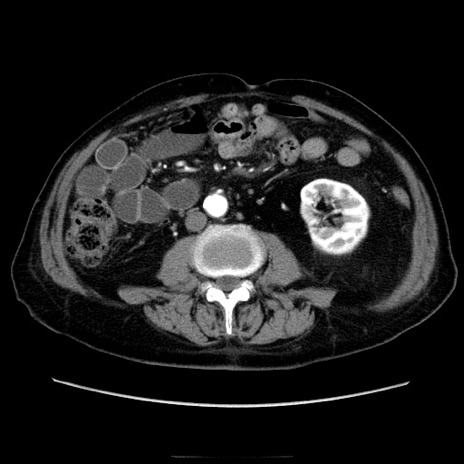

症例21(横断像)

【症例】70歳代男性

【主訴】腹痛

【現病歴】肝硬変・肝細胞癌にてかかりつけの方。約9時間前に食後より腹痛出現。症状が徐々に増悪し、嘔吐出現したため来院。

【既往歴】肝硬変、肝細胞癌(RFA、TACE後)

【身体所見】意識清明、表情苦悶様、BT 36℃、BP 129/78mmHg、P 88bpm、SpO2 97%(RA)、右上腹部から心窩部にかけて圧痛あり、反跳痛なし、筋性防御あり。

【データ】WBC 5800、CRP 0.16